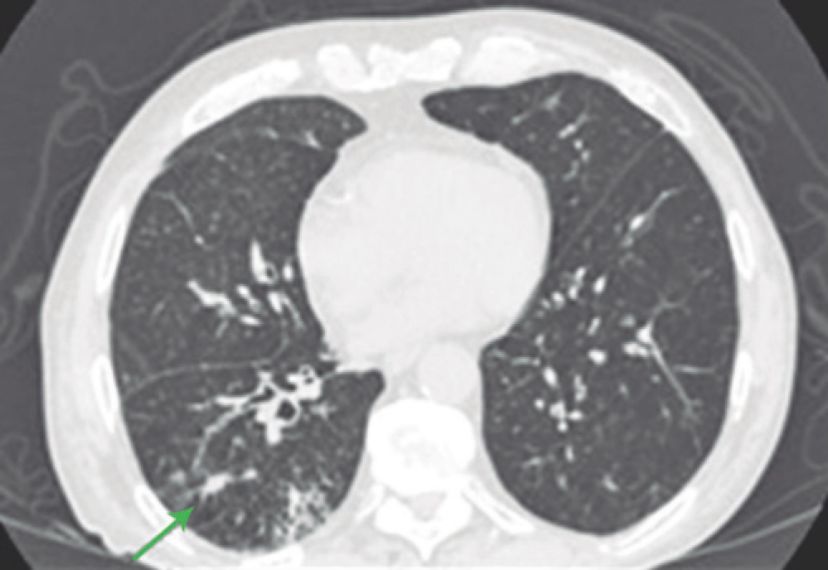

患者是一名54岁的老年男性,被确诊为肺大细胞神经内分泌癌,并且已经出现了转移。最初,病人使用了卡铂和紫杉醇进行治疗,随后又使用了顺铂和依托泊苷,同时接受了定向放疗。但是传统治疗的疗效并不理想,病人很快出现了中枢神经系统和肝脏的转移,因此帕博利珠单抗每3周2mg/kg的治疗方案再次临危上阵。在治疗5个疗程后,病人开始出现呼吸困难和咳嗽(无发热),氧饱和度仅为84%,CT检查显示其双肺出现了磨玻璃样变性。因此,病人开始每6小时使用哌拉西林-他唑巴坦4.5g的甲羟泼尼松2mg/kg进行治疗,在治疗开始后的24小时内,病人的肺部病情就出现了好转,治疗1周后的CT检查显示,病人肺部原先的浑浊阴影几乎全部消失。